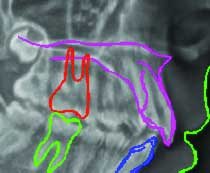

Using detection and classification algorithms, Logicon Software automatically highlights possible abnormalities in dental radiographs, calculates the probability that decay is present and recommends whether a restoration should be considered. Results are displayed based on a database of histological validated caries. The software extracts image features and correlates them with a database of known caries problems.

New for Logicon Software is the addition of a PreScan feature that further automates caries detection and improves practice efficiency. With a single click, practitioners can use the PreScan feature to automatically scan all interproximal surfaces in a bitewing radiograph and immediately display the results, instead of having to scan one interproximal surface at a time. Dentists then have access to an index of the results that correlate to each interproximal surface. This provides practitioners with an initial assessment of the state of caries.

Additional features of Logicon Software include a region of interest (ROI) adjustment tool that automatically searches to find maximum caries depth, as well as a zoom tool that allows practitioners to focus on specific regions. The software also makes working with third parties easier, as information and screenshots can be quickly sent via the software’s email function.